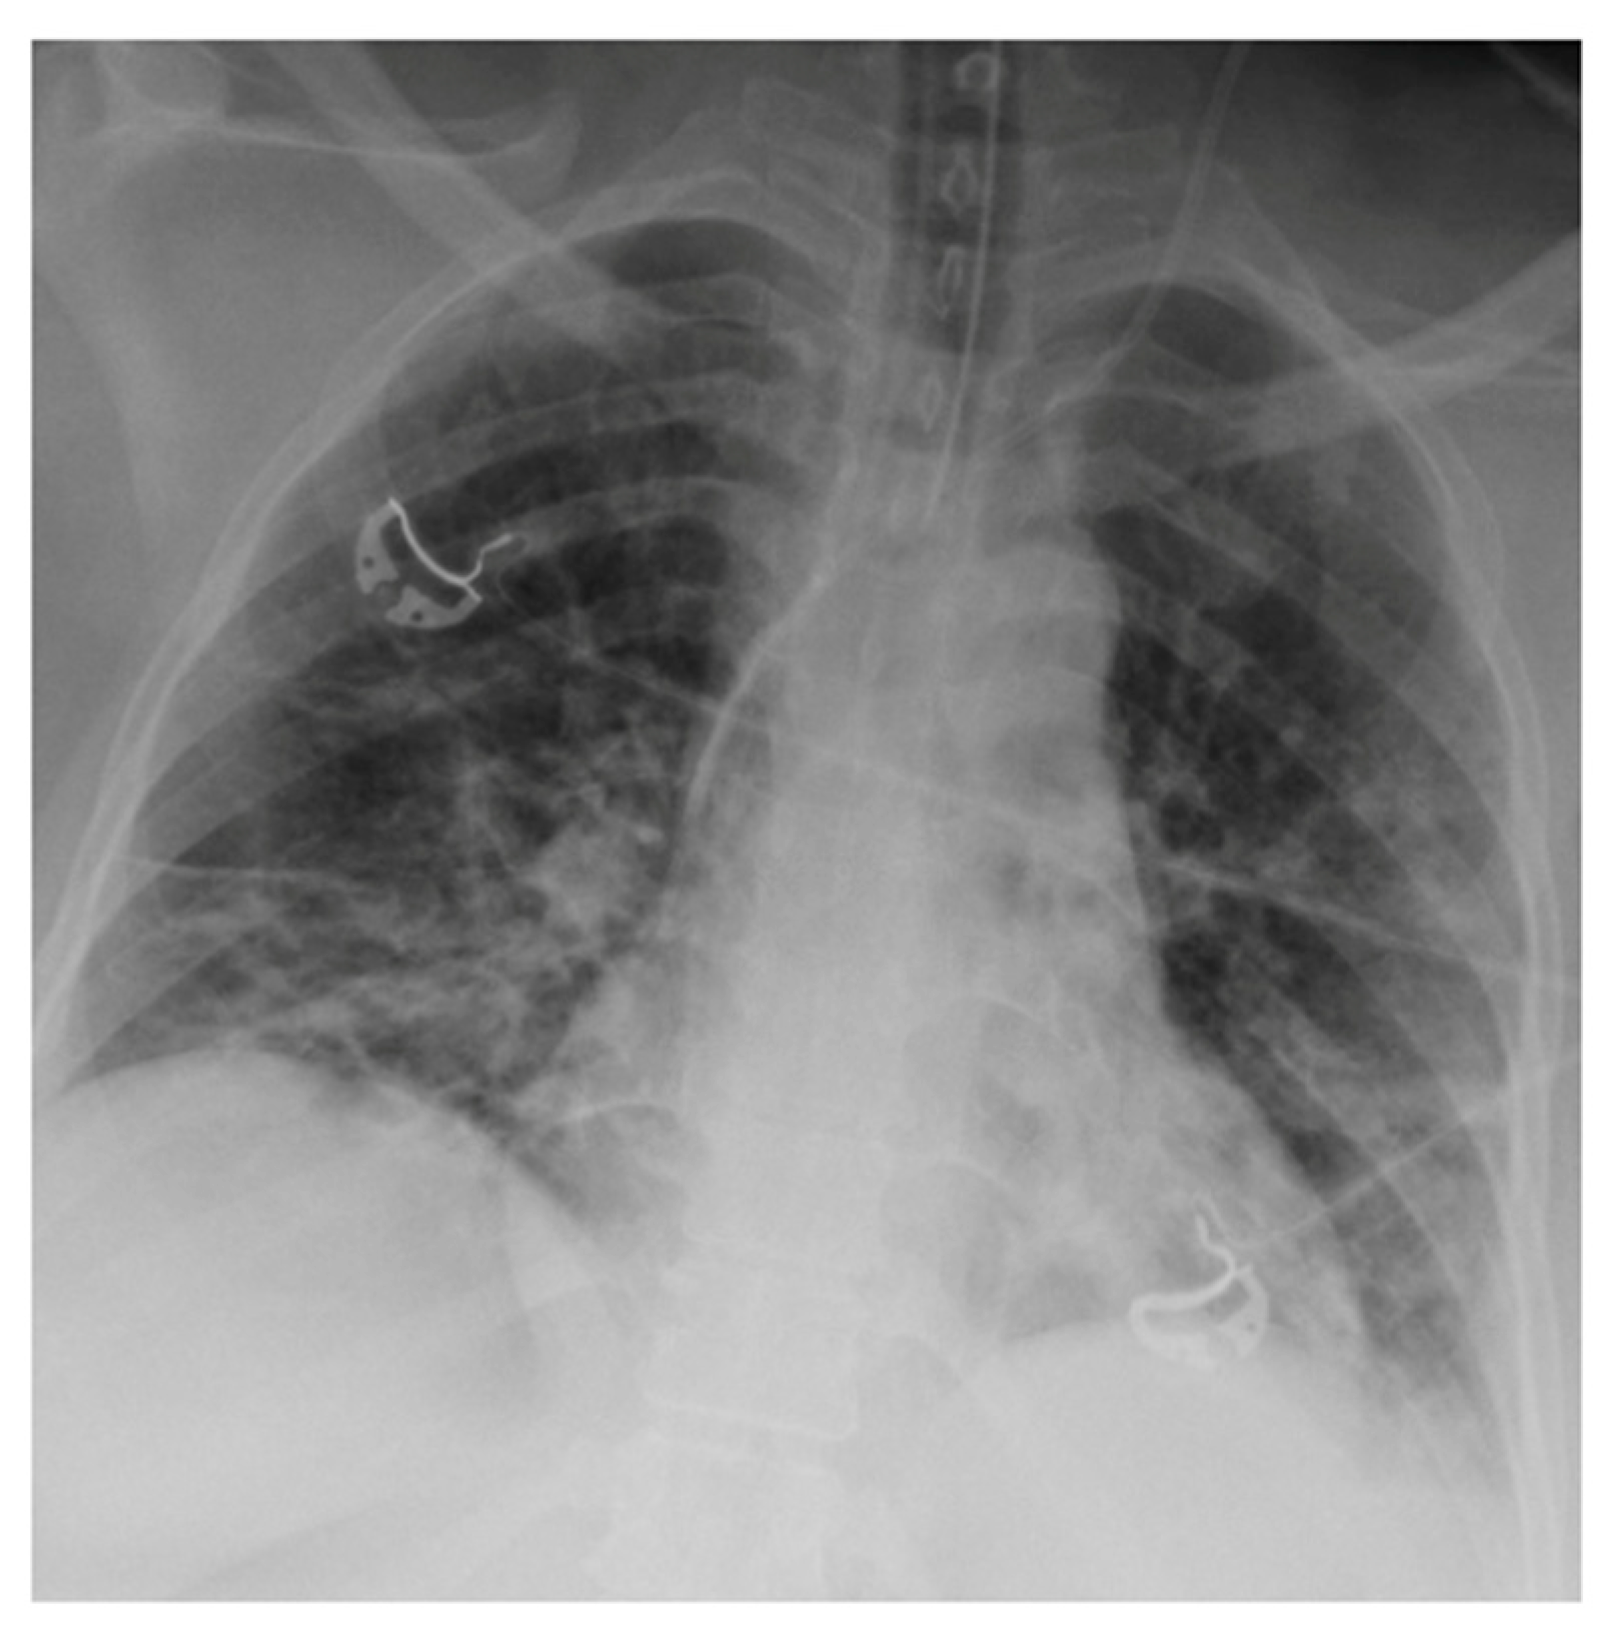

2.3. Imaging and Analysis

3. Results